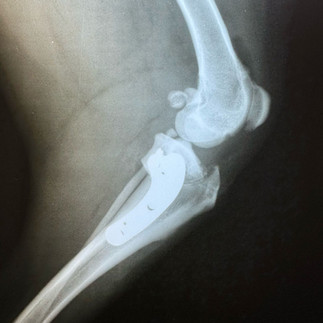

Siamo lieti di presentare alla nostra clientela la nuova Radiologia Digitale Diretta ad alta definizione, in grado di offrire ai nostri pazienti una diagnostica per immagini ancora più affidabile e sicura, soluzione che bypassa le limitazioni delle tecnologie precedenti. La nuova radiologia digitale rappresenta un avanzamento significativo rispetto al passato consentendo una diagnosi più rapida e precisa.

Le immagini vengono acquisite, visualizzate e archiviate in formato elettronico in modo da permettere una gestione più efficiente dei dati migliorando così la cura dei nostri animali.